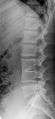

Several congenital block vertebrae in the transition from the thoracic to the lumbar spine and hemivertebrae.